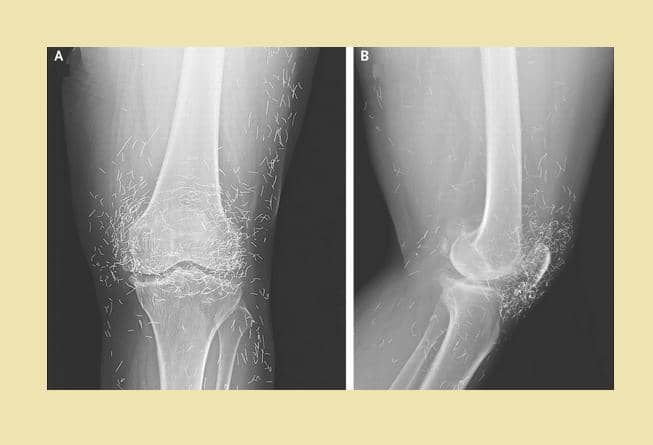

1. Ratusan susuk terlihat jelas lewat hasil foto sinar-X

Dalam unggahannya itu, Tasqia menuliskan bahwa ia sedang menangani seorang pasien berusia 55 tahun yang ingin melakukan X-ray atau sinar-X. Tak disangka, hasil foto sinar-X pasien tersebut memperlihatkan ratusan atau bahkan ribuan benda asing berbentuk seperti jarum yang bersarang pada tubuh pasiennya itu. Tasqia pun menyebut benda tersebut sebagai susuk. Sangking banyaknya, Tasqia pun tak tahu pasti berapa jumlah susuk yang ada pada bagian tubuh pasiennya itu.

Menurut Tasqia, dalam bahasa Inggris, ia menyebut susuk sebagai charm needle. Hal ini lantaran bentuknya yang seperti jarum. Susuk juga menurut Tasqia bisa berubah posisi ketika dilakukan foto sinar-X lagi.

"Masih banyak yang gatau susuk ya wkwkw bahasa inggrisnya 'charm needle' karena bentuknya juga kayak jarum. Biasanya kalo di foto X-ray lagi, nanti berubah posisinya," tulis Tasqia.

Ketika ditanya biasanya susuk banyak ditemukan di area tubuh yang mana, Tasqia menjawab bahwa susuk bisa dimasukkan di mana saja. Namun, biasanya banyak ditemukan di sekitar kepala dan sisanya ada sekitar area kaki hingga payudara.

"LMAOOOO yess bisa dimana ajaaa cuma emang umumnya di daerah kepala, sisanya bisa di kaki tangan, perut, dada, payudara, dll," tulisnya.